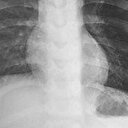

Ailesine durumdan bahsetmeyen Dolanbay, ertesi gün karın ağrısıyla hastaneye gitti. Tedavi altına alınan genç kızdan, iğnelerden 3'ü doğal yolla, midede ve ince bağırsakta bulunan 3 iğne de endoskopi yöntemiyle çıkarıldı. Kalan 9 iğnenin bağırsağın ilerisinde ve kalın bağırsakta olduğu öğrenildi. Dolanbay, gözlem altına alındı. Gözlem sonucunda doğal yolla çıkmayan iğnelerin, kolonoskopi yöntemi ile alınacağı bildirildi.

Mide ve ince bağırsaklara saplanan iğneler çıkartıldı. Çocuk Gastroenteroloji Anabilim Dalı Başkanı Prof. Dr. Yaşar Doğan ise, "Şuanda gözetimimiz altında. Yaklaşık 24 saat izlememize rağmen iğnelerin bazıları bağırsakta ve mide de olduğundan dolayı endoskopi yaptık. Mideye ve ince bağırsağa saplanmış olan iğneleri çıkardık" diye konuştu.